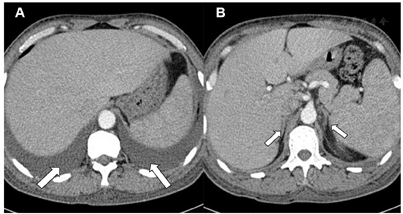

患者男性,49岁,主因"皮肤变黑、浮肿4年"于2017年12月就诊。2014年患者无明显诱因出现全身肤色变黑伴双下肢浮肿,浮肿逐渐蔓延至全身,尿量较前减少,每日尿量约900 ml。无发热、盗汗、咳嗽、咳痰,无胸闷、憋气,无尿中泡沫、尿色改变,未诊治。2016年7月外院查血常规白细胞4.83×109/L、中性粒细胞48.9%、血红蛋白148 g/L、血小板186×109/L。尿常规尿潜血(),蛋白(-)。血沉16 mm/h。ANA+dsDNA(-),抗ENA(-)。2017年3月外院查血白蛋白34.6 g/L、校正后血Ca2+ 2.12 mmol/L、Na+ 143.3 mmol/L、肌酐81 μmol/L(正常参考范围30~110,下同)。2017年4月来我院进一步检查:清晨血总皮质醇6.09 μg/dl(4.0~22.3)、血浆ACTH 127.0 pg/ml(0~46)、24 h尿游离皮质醇17.78 μg/24 h(12.3~103.5)。甲状腺功能FT3 1.92~2.82 pg/ml(1.80~4.10)、FT4 0.864~0.980 ng/dl(0.81~1.89)、TSH 5.873~7.896 mIU/L(0.38~4.34)、TPO-Ab、TG-Ab阴性。性激素5项LH 12.71 IU/L(1.24~8.62)、FSH 14.21 IU/L(1.27~19.26)、睾酮1.65 ng/ml(1.75~7.81)、雌二醇54.00 pg/ml(<47.00)、孕酮0.37 ng/ml(0.10~0.84)。空腹血糖4.9 mmol/L、血清Na+ 141 mmol/L、K+ 4.0 mmol/L、白蛋白32~35 g/L、校正后血Ca2+ 1.84~2.08 mmol/L(2.13~2.70)、磷1.48~1.60 mmol/L(0.81~1.45)、PTH 67.1 pg/ml(12.0~68.0)、25-羟维生素D3 9.8 ng/ml(8.0~50.0)。肾上腺CT平扫+增强示双侧肾上腺大小形态密度未见明显异常,脾大,肝周及脾周积液,双侧胸腔积液(图1)。考虑原发性肾上腺皮质功能减退(Addison病),自身免疫多腺体综合征(APS)不除外,予氢化可的松20 mg/次,1次/d治疗1个月后复查清晨血浆ACTH 143.0 pg/ml。期间患者出现食欲下降,性功能减退表现。2017年7月因反复咳嗽于当地住院检查胸部CT示右侧胸腔积液,进行胸腔穿刺检查,胸水常规:淡黄色,无凝块,白细胞130×106/L、中性粒细胞55%、淋巴细胞45%、红细胞8 000×106/L。胸水生化:总蛋白37.8 g/L(0.0~25.0)、葡萄糖5.9 mmol/L(3.89~6.11)、腺苷脱氨酶2.78 U/L(0~25)。胸水结核菌涂片(-)。予喹诺酮类抗生素治疗后症状稍减轻,2017年8月再次因咳嗽就诊呼吸科后建议进一步除外结核感染。2017年10月复查清晨血总皮质醇4.8 μg/dl、血浆ACTH 81.4 pg/ml、硫酸脱氢表雄酮42.0 μg/dl(70~495)、PTH 63.1 pg/ml、校正后游离钙1.06 mmol/L(1.08~1.28)、空腹血糖4.8 mmol/L、餐后2 h血糖7.0 mmol/L,IgG4正常。发病以来患者精神、体力可,近4个月出现胸闷、憋气,夜间不能平卧,大便每天1次,尿量偏少,每日约800~900 ml。体重变化不大。否认肢体麻木、出汗异常、排尿及排便困难和起立后头晕。既往体健。个人史和家族史无特殊。

注:A:腹腔积液,肝周、脾周均可见积液(箭头所指);B:双侧肾上腺大小形态基本正常(箭头所指)